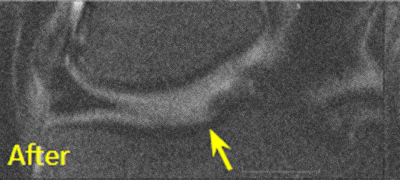

BEFORE And AFTER Imaging Results

Below are the outcomes of two patients with Regenexx protocol done for knee osteoarthritis. Scroll the arrow to the right to see the MRI of the knee joint before their treatment — the white/ lighter area indicates damage. Scroll to the left to see the MRI of the knee joint after their treatment.

Patient 1 MRI: 51 years old

- Patient 1: The patient was unable to return to many activities after unsuccessful microfracture surgery. As a result, underwent percutaneous, autologous, mesenchymal stem cell implant, after which they were able to return to their daily activities.